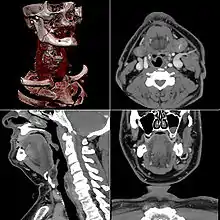

Head

CT scanning of the head is typically used to detect infarction (stroke), tumors, calcifications, haemorrhage, and bone trauma.[32] Of the above, hypodense (dark) structures can indicate edema and infarction, hyperdense (bright) structures indicate calcifications and haemorrhage and bone trauma can be seen as disjunction in bone windows. Tumors can be detected by the swelling and anatomical distortion they cause, or by surrounding edema. CT scanning of the head is also used in CT-guided stereotactic surgery and radiosurgery for treatment of intracranial tumors, arteriovenous malformations, and other surgically treatable conditions using a device known as the N-localizer.[33][34][35][36][37][38]

Neck

Contrast CT is generally the initial study of choice for neck masses in adults.[39] CT of the thyroid plays an important role in the evaluation of thyroid cancer.[40] CT scan often incidentally finds thyroid abnormalities, and so is often the preferred investigation modality for thyroid abnormalities.[40]